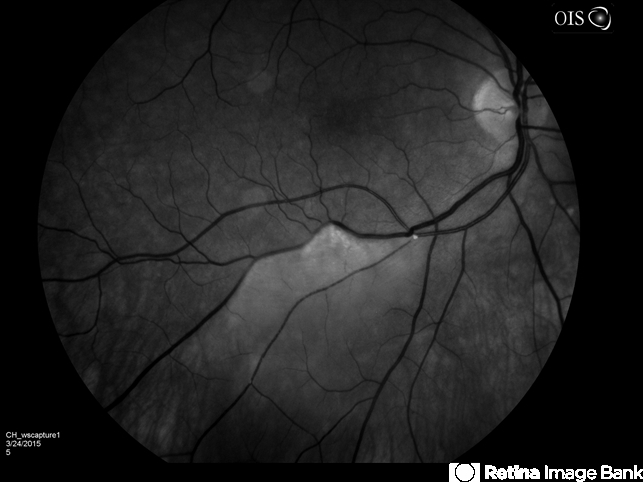

- branch retinal artery occlusion (BRAO), hollenhorst plaque

- Branch retinal artery occlusion with a Hollenhorst Plaque.